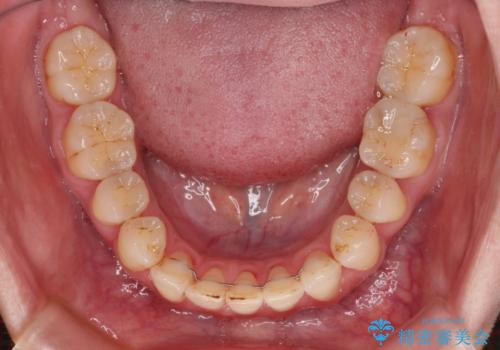

- 上下前歯の隙間を気にして来院された患者様です。

下顎前歯が1本欠損しており、上下小臼歯はクロスバイトとなり、上下前歯の接触もないという不正咬合の状態でした。

クロスバイトはワイヤー矯正が得意とするところであり、上下前歯の非接触や開咬はインビザラインの得意とするところであるので、ワイヤー装置により事前にクロスバイトを改善し、その後にインビザラインにて仕上げていくこととしました。

奥歯の咬み合わせに問題がある場合、インビザラインでは改善できないことが多々あります。事前にワイヤー装置により問題点を解消しておくことで、スムーズにインビザラインでの矯正治療を進めていくことができます。